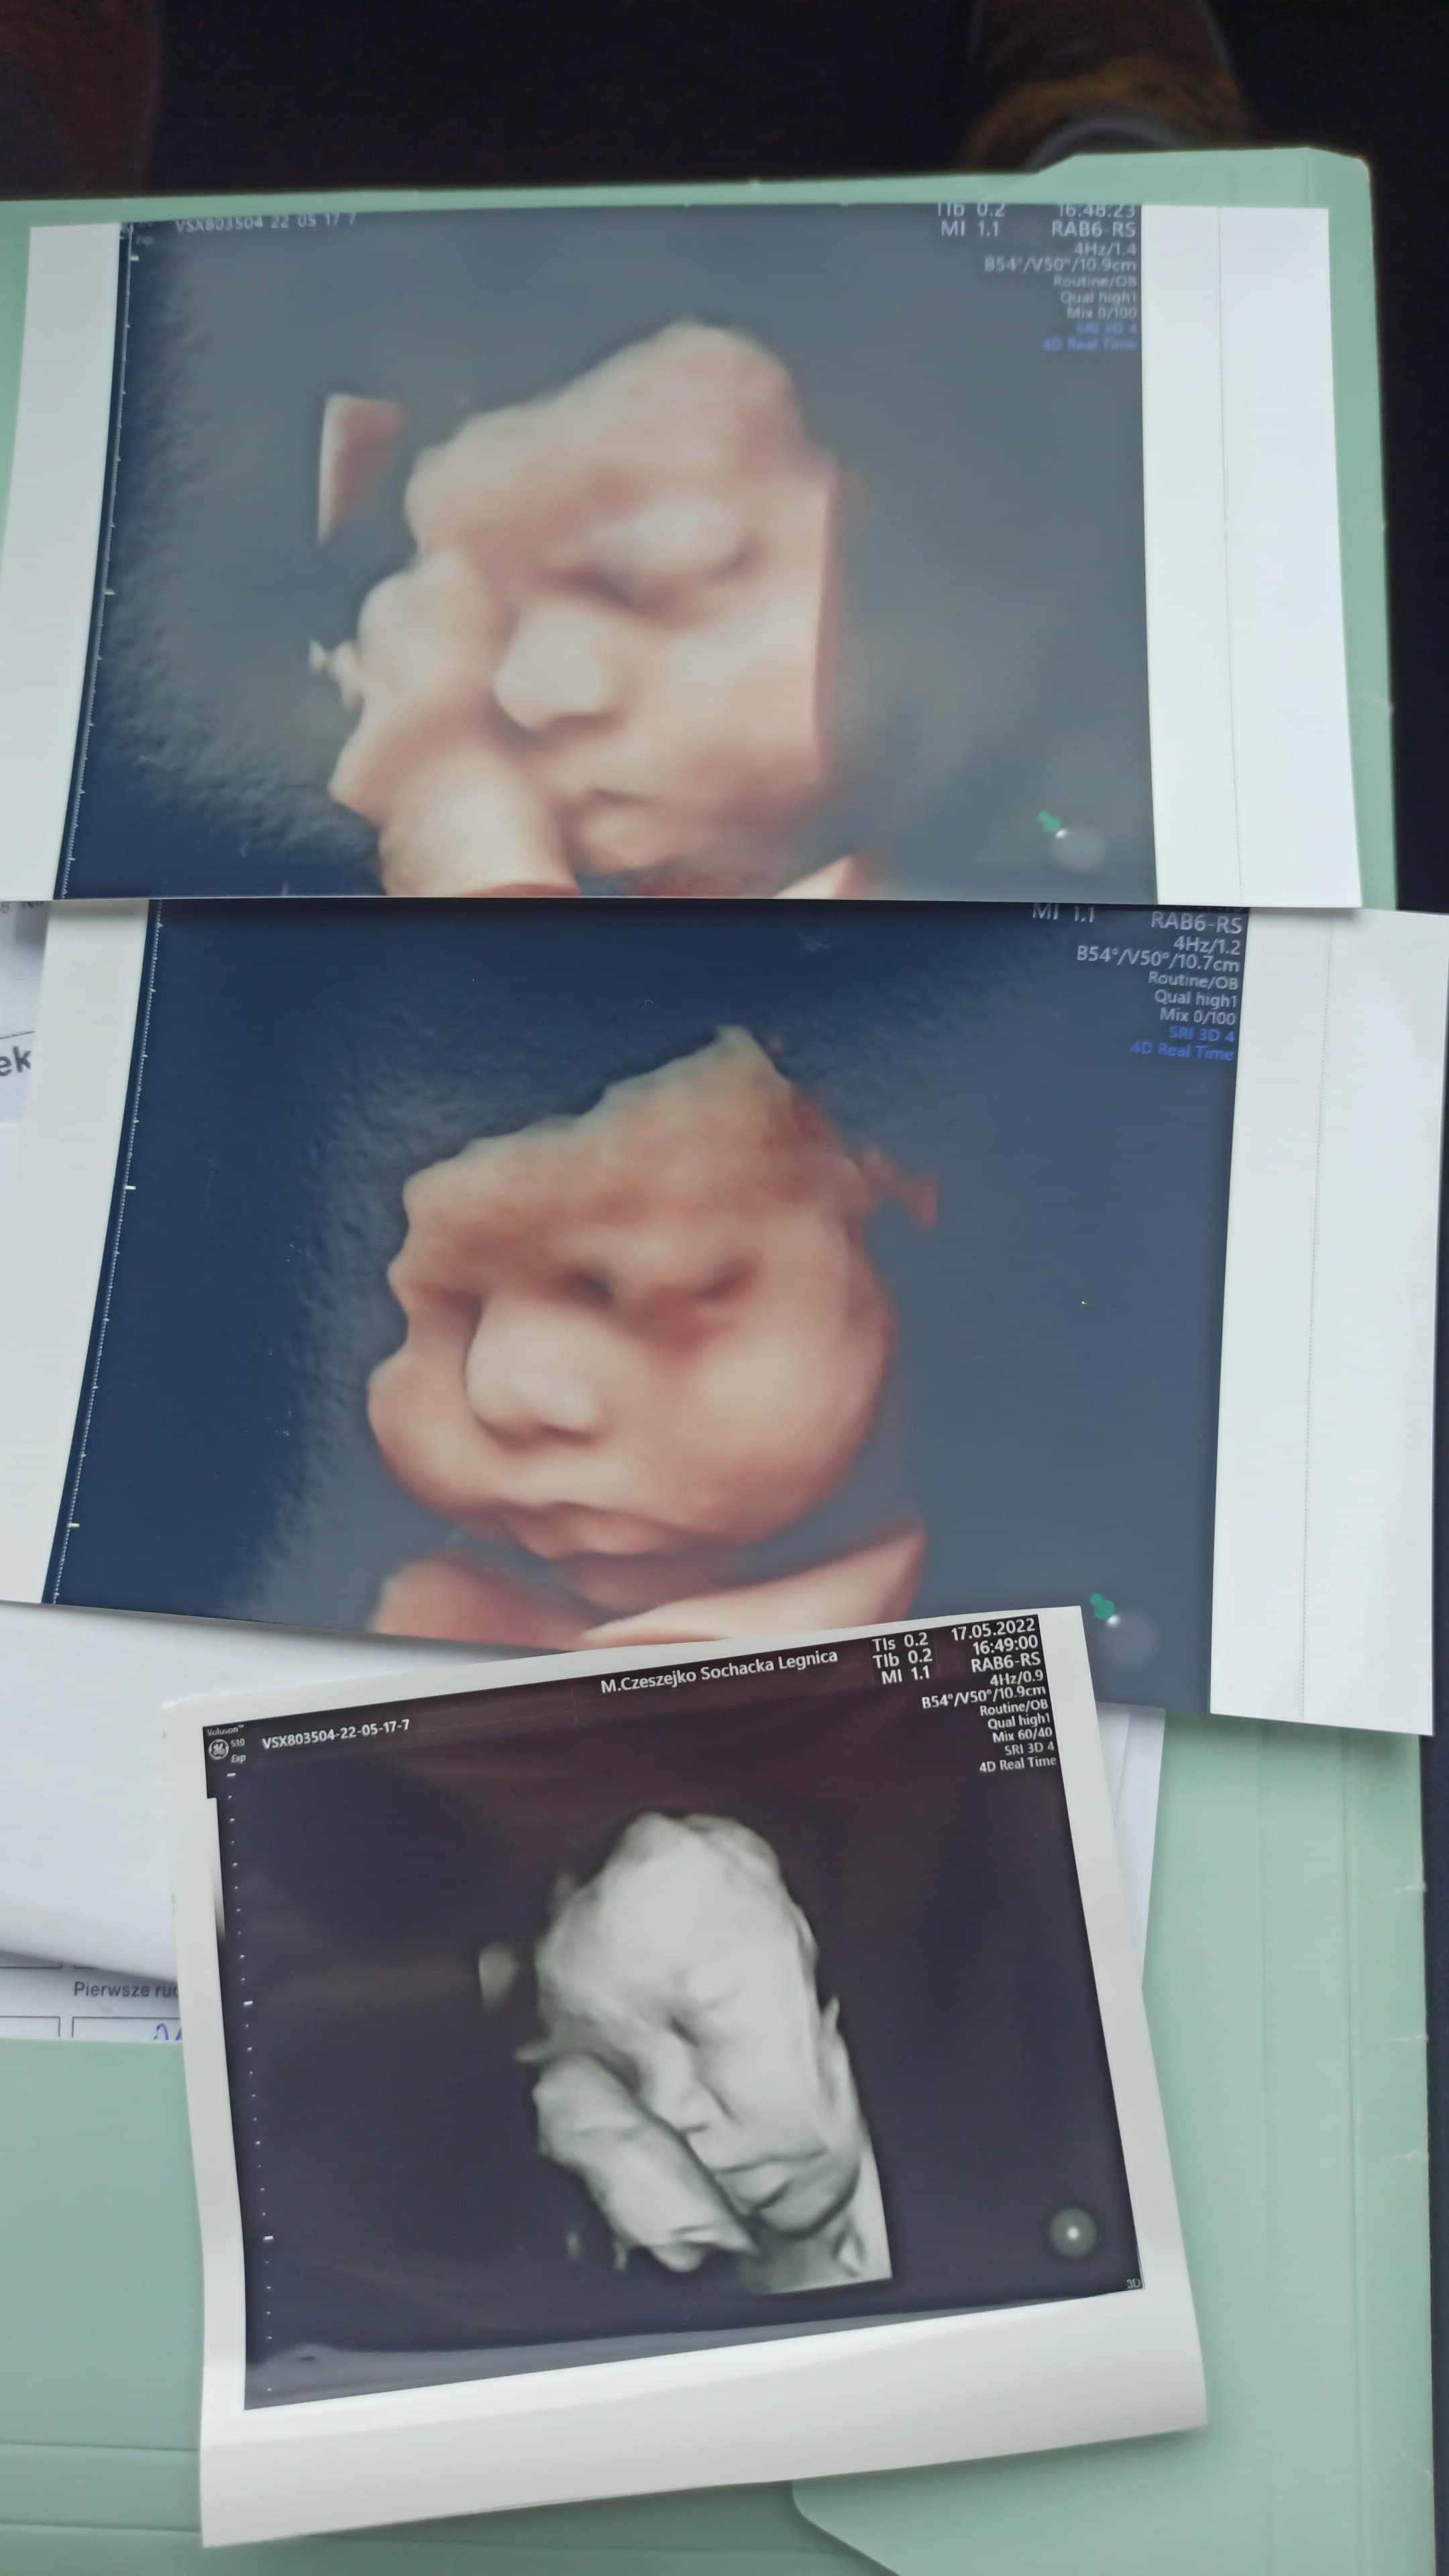

Myślę, że tak i mogę się podzielić. Dla porównania zdjęcie 3d z bodajże 30 tygodnia i kilka dni po porodzie.